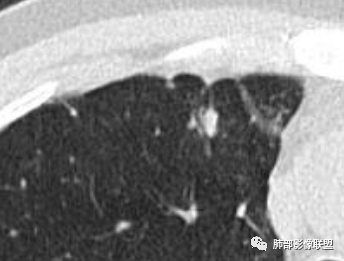

1.临床特点:52岁男性,体检发现肺结节。有吸烟史。非小细胞肺癌相关抗原与神经元烯醇化酶轻度升高。2.影像特点:右肺上叶前段可见不规则结节影,整体膨隆,可见浅分叶,周围局部可见边界清楚的磨玻璃影。可见血管集束征及脐凹征,临近叶间胸膜受牵拉凹陷,局部支气管到达病灶边缘后显示截断。3.病例小结:中老年吸烟男性,右肺上叶前段不规则结节,膨胀感较明显,收缩力强,支气管截断,加上边界清楚的磨玻璃影。符合浸润性腺癌表现。

4.相关知识:浸润性肺腺癌分为:附壁状、腺泡状、乳头状、微乳头状、实体型,较少见的生长模式包括浸润性黏液型、胶样、肠型和胎儿型。腺癌影像表现为磨玻璃影、部分实性结节、实性结节或实变。